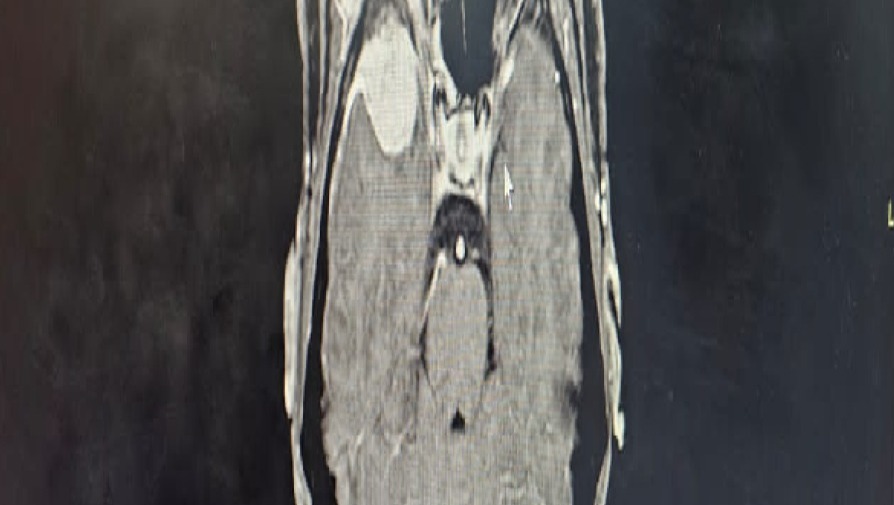

Lamentablemente la enfermedad volvió, y nuevamente está activa en el cuello; pero eso no es todo. Ahora también me han detectado un tumor en la cabeza.

Lamentablemente no tenemos los recursos necesarios para realizar las biopsias en mi cuello y cabeza, exámenes, placas y medicinas que nos dirán a qué clase de cáncer me estoy enfrentando.

Es urgente realizarme una Craneotomía, para luego comenzar las quimioterapias y radioterapias que sean requeridas, con la esperanza de sanar definitivamente.